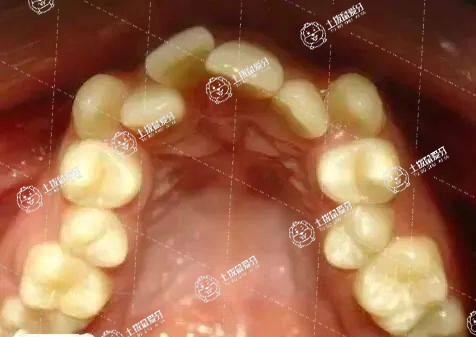

牙齒深覆合矯正的容易程度取決于患者錯(cuò)頜畸形的類型和嚴(yán)重程度。深覆合只是錯(cuò)頜畸形中的一類,醫(yī)生會(huì)判斷患者是深覆合的哪一類,如果患者只是一個(gè)簡單的牙齒深覆合,就比較容易矯正;但如果患者的上下頜骨之間都有問題,即骨性有問題,可能要矯正就較復(fù)雜,甚至有時(shí)還需要正頜外科的介入。牙齒的深覆合即患者的上頜牙咬合,超過下頜牙的1/3。這時(shí)患者的咀嚼力會(huì)降低,牙齒會(huì)經(jīng)常發(fā)生磨損和磨耗;還有患者咬的過緊的時(shí)候會(huì)對(duì)關(guān)節(jié)造成很大的壓力,咀嚼力低同時(shí)也會(huì)加重胃腸道負(fù)擔(dān)。

牙齒深覆頜矯正的難度是比較大的,具體的難度系數(shù)主要是取決于嚴(yán)重程度以及畸形的類型。一般深覆合是屬于錯(cuò)頜畸形當(dāng)中的其中一種類型,如果是比較簡單的牙齒深覆頜,矯正的難度是比較低的,如果是屬于骨性的問題,矯正比較復(fù)雜,治療難度比較大,可能還需要介入正頜外科手術(shù)來進(jìn)行治療。

深覆合矯正的成功率是比較高的。但是具體深覆合矯正的難易程度是取決于患者具體的錯(cuò)頜畸形的類型以及嚴(yán)重程度有一定關(guān)系的。如若只是進(jìn)行簡單的牙齒深覆合,難度系數(shù)并不大,是非常容易的;但若是患者比較嚴(yán)重,比如上下頜骨之間都有問題的情況下,進(jìn)行矯正是比較復(fù)雜的,有的患者甚至需要做正頜外科的介入來協(xié)助治療。但是無論難易程度如何,成功率都是非常高的。